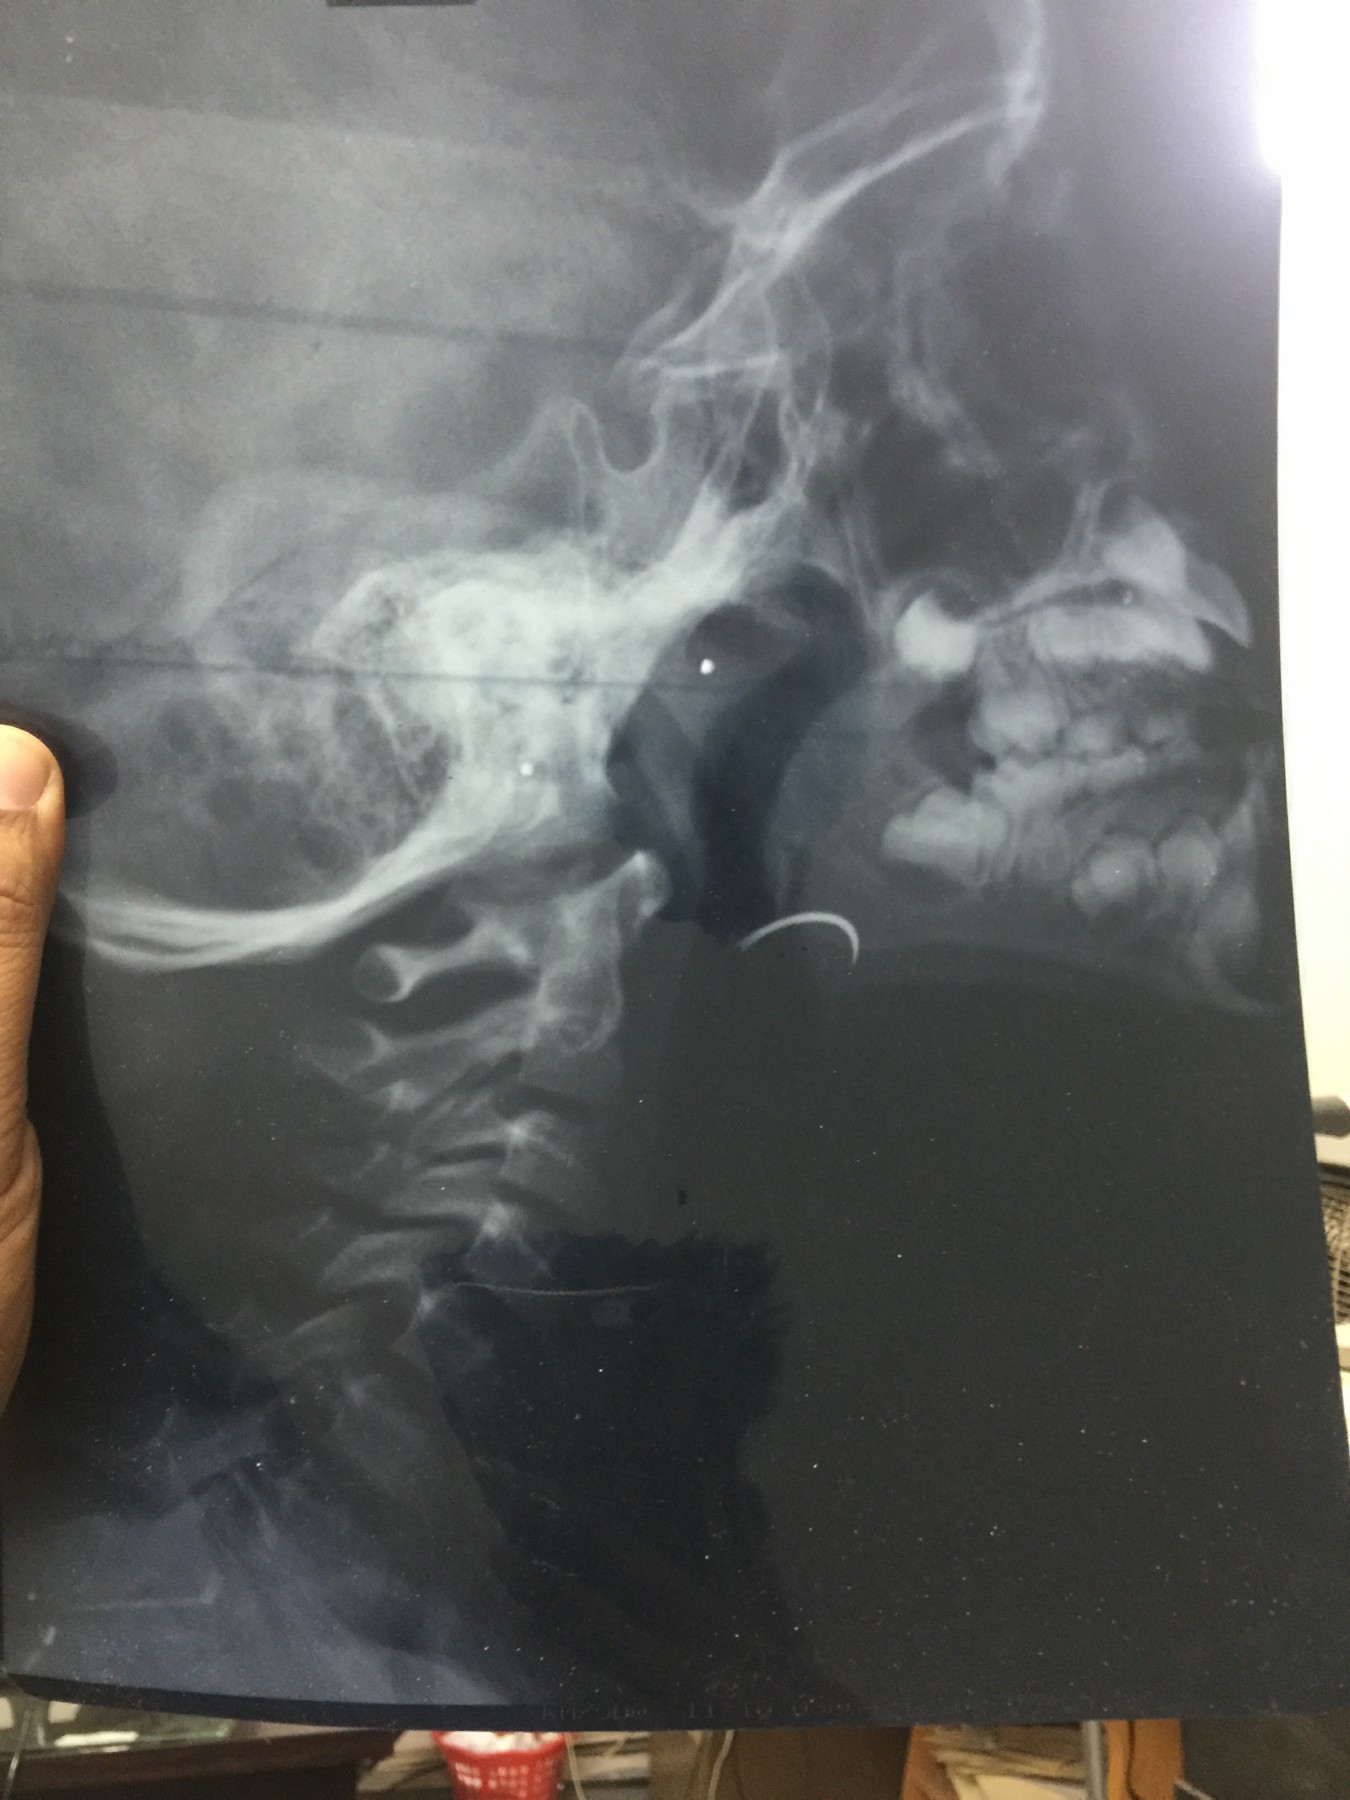

شهد مسلسل الإهمال الطبى حلقة جديدة بمستشفى جامعة طنطا، حيث نسى أحد الأطباء إبرة الخياطة الخاصة بالجروح داخل حنجرة أحد الأطفال خلال إجراء علمية جراحية لإزالة اللوزتين.

وأكد والد الطفل، أن الطبيب اكتشف أنه نسي الإبرة داخل زور نجله، وقام بتخدير نجله مرة ثانية لإخراج الإبرة ولكن دون فائدة، مؤكدا أن الطبيب أكد انه لن يستطيع استخراج الإبرة من الطفل.

وأكد، أنه توجه للدكتور أمجد عبد الرؤوف عميد كلية الطب، والدكتور هشام توفيق المشرف العام على المستشفيات الجامعية للتدخل لإنقاذ نجله، مشيرا إلى أنه تقدم بشكوى ضد الطبيب الذي أجرى العملية “أ.س” لرئيس قسم الأنف والأذن بالمستشفى، وعميد كلية الطب والمشرف العام على المستشفيات الجامعية، مؤكدا أن رئيس قسم الأنف والأذن والحنجرة، استدعى أطباء من خارج المستشفى لإنقاذ نجله، وأكدوا أن فى ذلك خطورة على حياته.